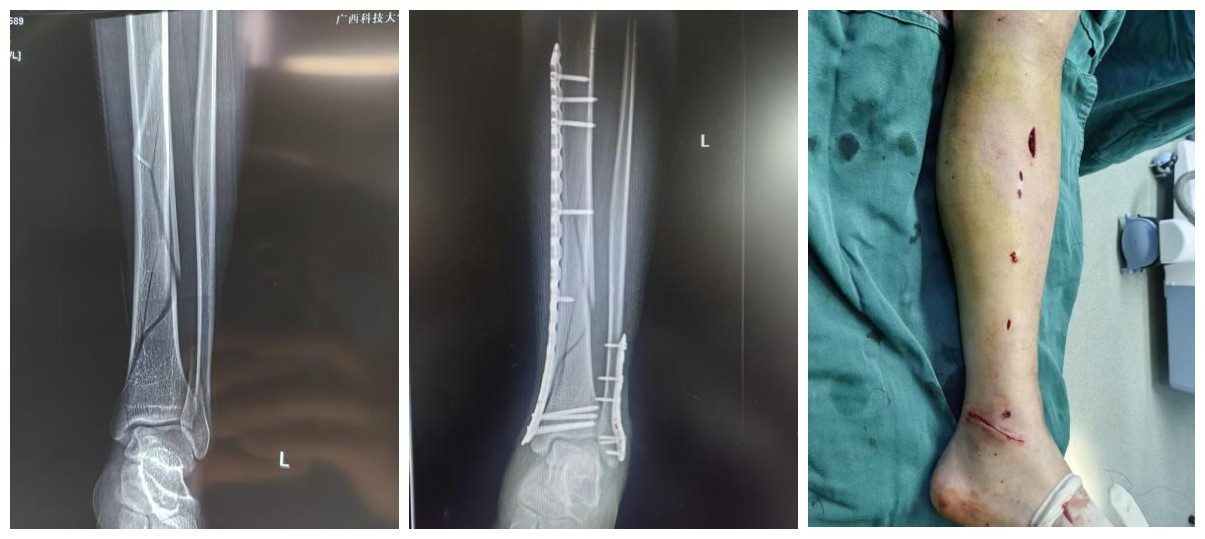

四肢复杂骨折、关节内骨折、骨盆髋臼骨折、老年骨质疏松性骨折;断指(肢)再植、手部先天畸形、周围神经卡压及损伤等。

(1)广泛开展MIPPO(微创经皮接骨板)技术,利用生物学固定原则,最大程度保护骨折端血运,促进骨折愈合;

(2)熟练运用髓内钉、锁定钢板等内固定技术,处理各类复杂骨折;